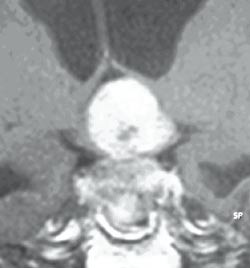

Tumorvekst

Hypofysesvulstene klassifiseres etter størrelse og utbredelse i flere ulike systemer (15, 16). De vokser først ekspansivt i hypofysegropen som etter hvert utvides, og hypofysen blir ofte skjøvet til siden eller oppover (fig 2). De kan bre seg kranialt og trykke på synsnervene og hjernen, og de kan vokse gjennom og inn i sinus cavernosus lateralt (17), og gjennom veggen mot sinus sfenoidale nedad og fremover (16). De kan noen ganger nå en betydelig størrelse før de blir diagnostisert, og kan da gi symptomer på forhøyet intrakranialt trykk, for eksempel ved avstengning av foramen Monroi og 3. ventrikkel med utvikling av obstruktiv hydrocephalus (fig 3).

Ved mistanke om svulst i hypofysegropen utføres MR. De fleste adenomer er også synlige på CT, som brukes ved kontraindikasjoner mot MR (pacemaker, magnetiske klips osv.). MR gjøres med 3 mm snittykkelse i sagittal- og koronalplanet før og etter injeksjon av gadoliniumkontrast, ev. supplert med aksiale T1- og T2-vektede bilder (fig 1 – 3). Ved synsaffeksjon skjer utredningen av svulsten i samarbeid mellom endokrinolog (koordinator), nevrokirurg, nevroradiolog, og øyelege. Pasientene drøftes på samarbeidsmøter, såkalte hypofysemøter (fig 4).